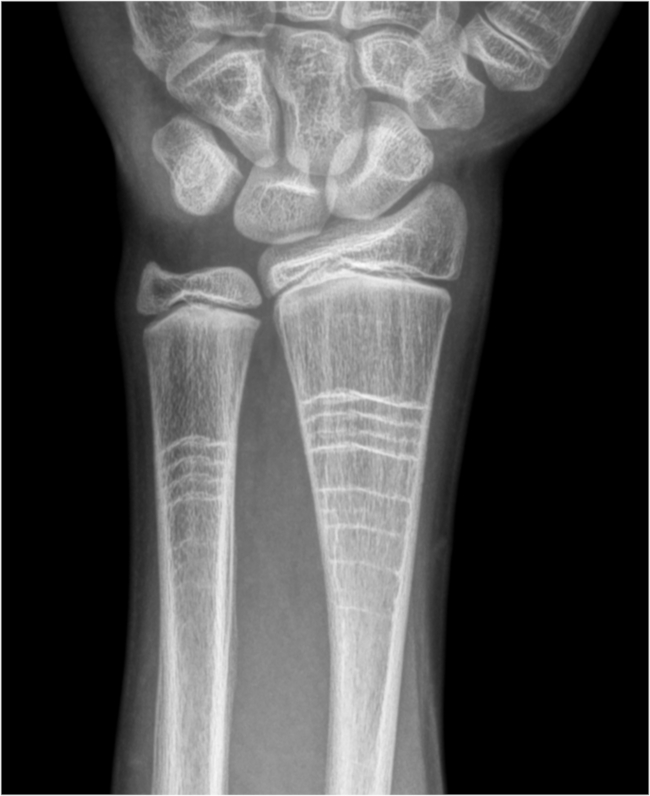

El signo radiológico de las líneas de cebra, se refiere a la aparición de bandas lineales de alta densidad ubicadas en la zona metafisaria de los huesos, paralelas al cartílago de crecimiento, que pueden evidenciarse en el estudio radiológico de los miembros (►Figura 1). Corresponden al reflejo del efecto de los bifosfonatos en el esqueleto en crecimiento y fue descrito en 2007 por Al Muderis y col.1

La acción de los bifofonatos radica en inactivar e inducir la apoptosis de osteoclastos, disminuyendo asimismo su reclutamiento y diferenciación.1 Cuando se administra el medicamento en el esqueleto inmaduro, se forma hueso denso en las metáfisis, que posteriormente con el crecimiento del hueso, se desplazará a la zona diafisaria. El proceso se repite mientras continúen los ciclos de tratamiento, dejando ese aspecto radiológico característico en huesos largos y esqueleto axial.1,2

La interpretación radiológica es simple si el antecedente de administración de bifosfonatos está presente. Una entidad diferencial son las líneas de Park -Harris, llamadas líneas de detención del crecimiento. Se observan en estudios radiológicos como líneas radiodensas paralelas al cartílago de crecimiento en huesos inmaduros que luego migran hacia la diáfisis. Se relacionó su aparición con detenciones temporales del crecimiento en contexto de enfermedad crónica, infección grave o alteración nutricional. A diferencia de las líneas cebra, pueden permanecer en la edad adulta con mayor frecuencia.2,3

En conclusión, el signo de las líneas de cebra, es un hallazgo radiológico llamativo que refiere a la aparición de bandas lineales densas ubicadas en la zona metafisaria de los huesos. Si bien carece de significación clínica, su presencia puede causar confusión, por lo que debe ser conocido por el médico radiólogo. Si, en un paciente con el esqueleto en crecimiento, conocemos el antecedente terapéutico con bifosfonatos cíclicos, el diagnóstico de estas lineas seria simple. De otra manera, diagnósticos diferenciales deberán ser tenidos en cuenta.